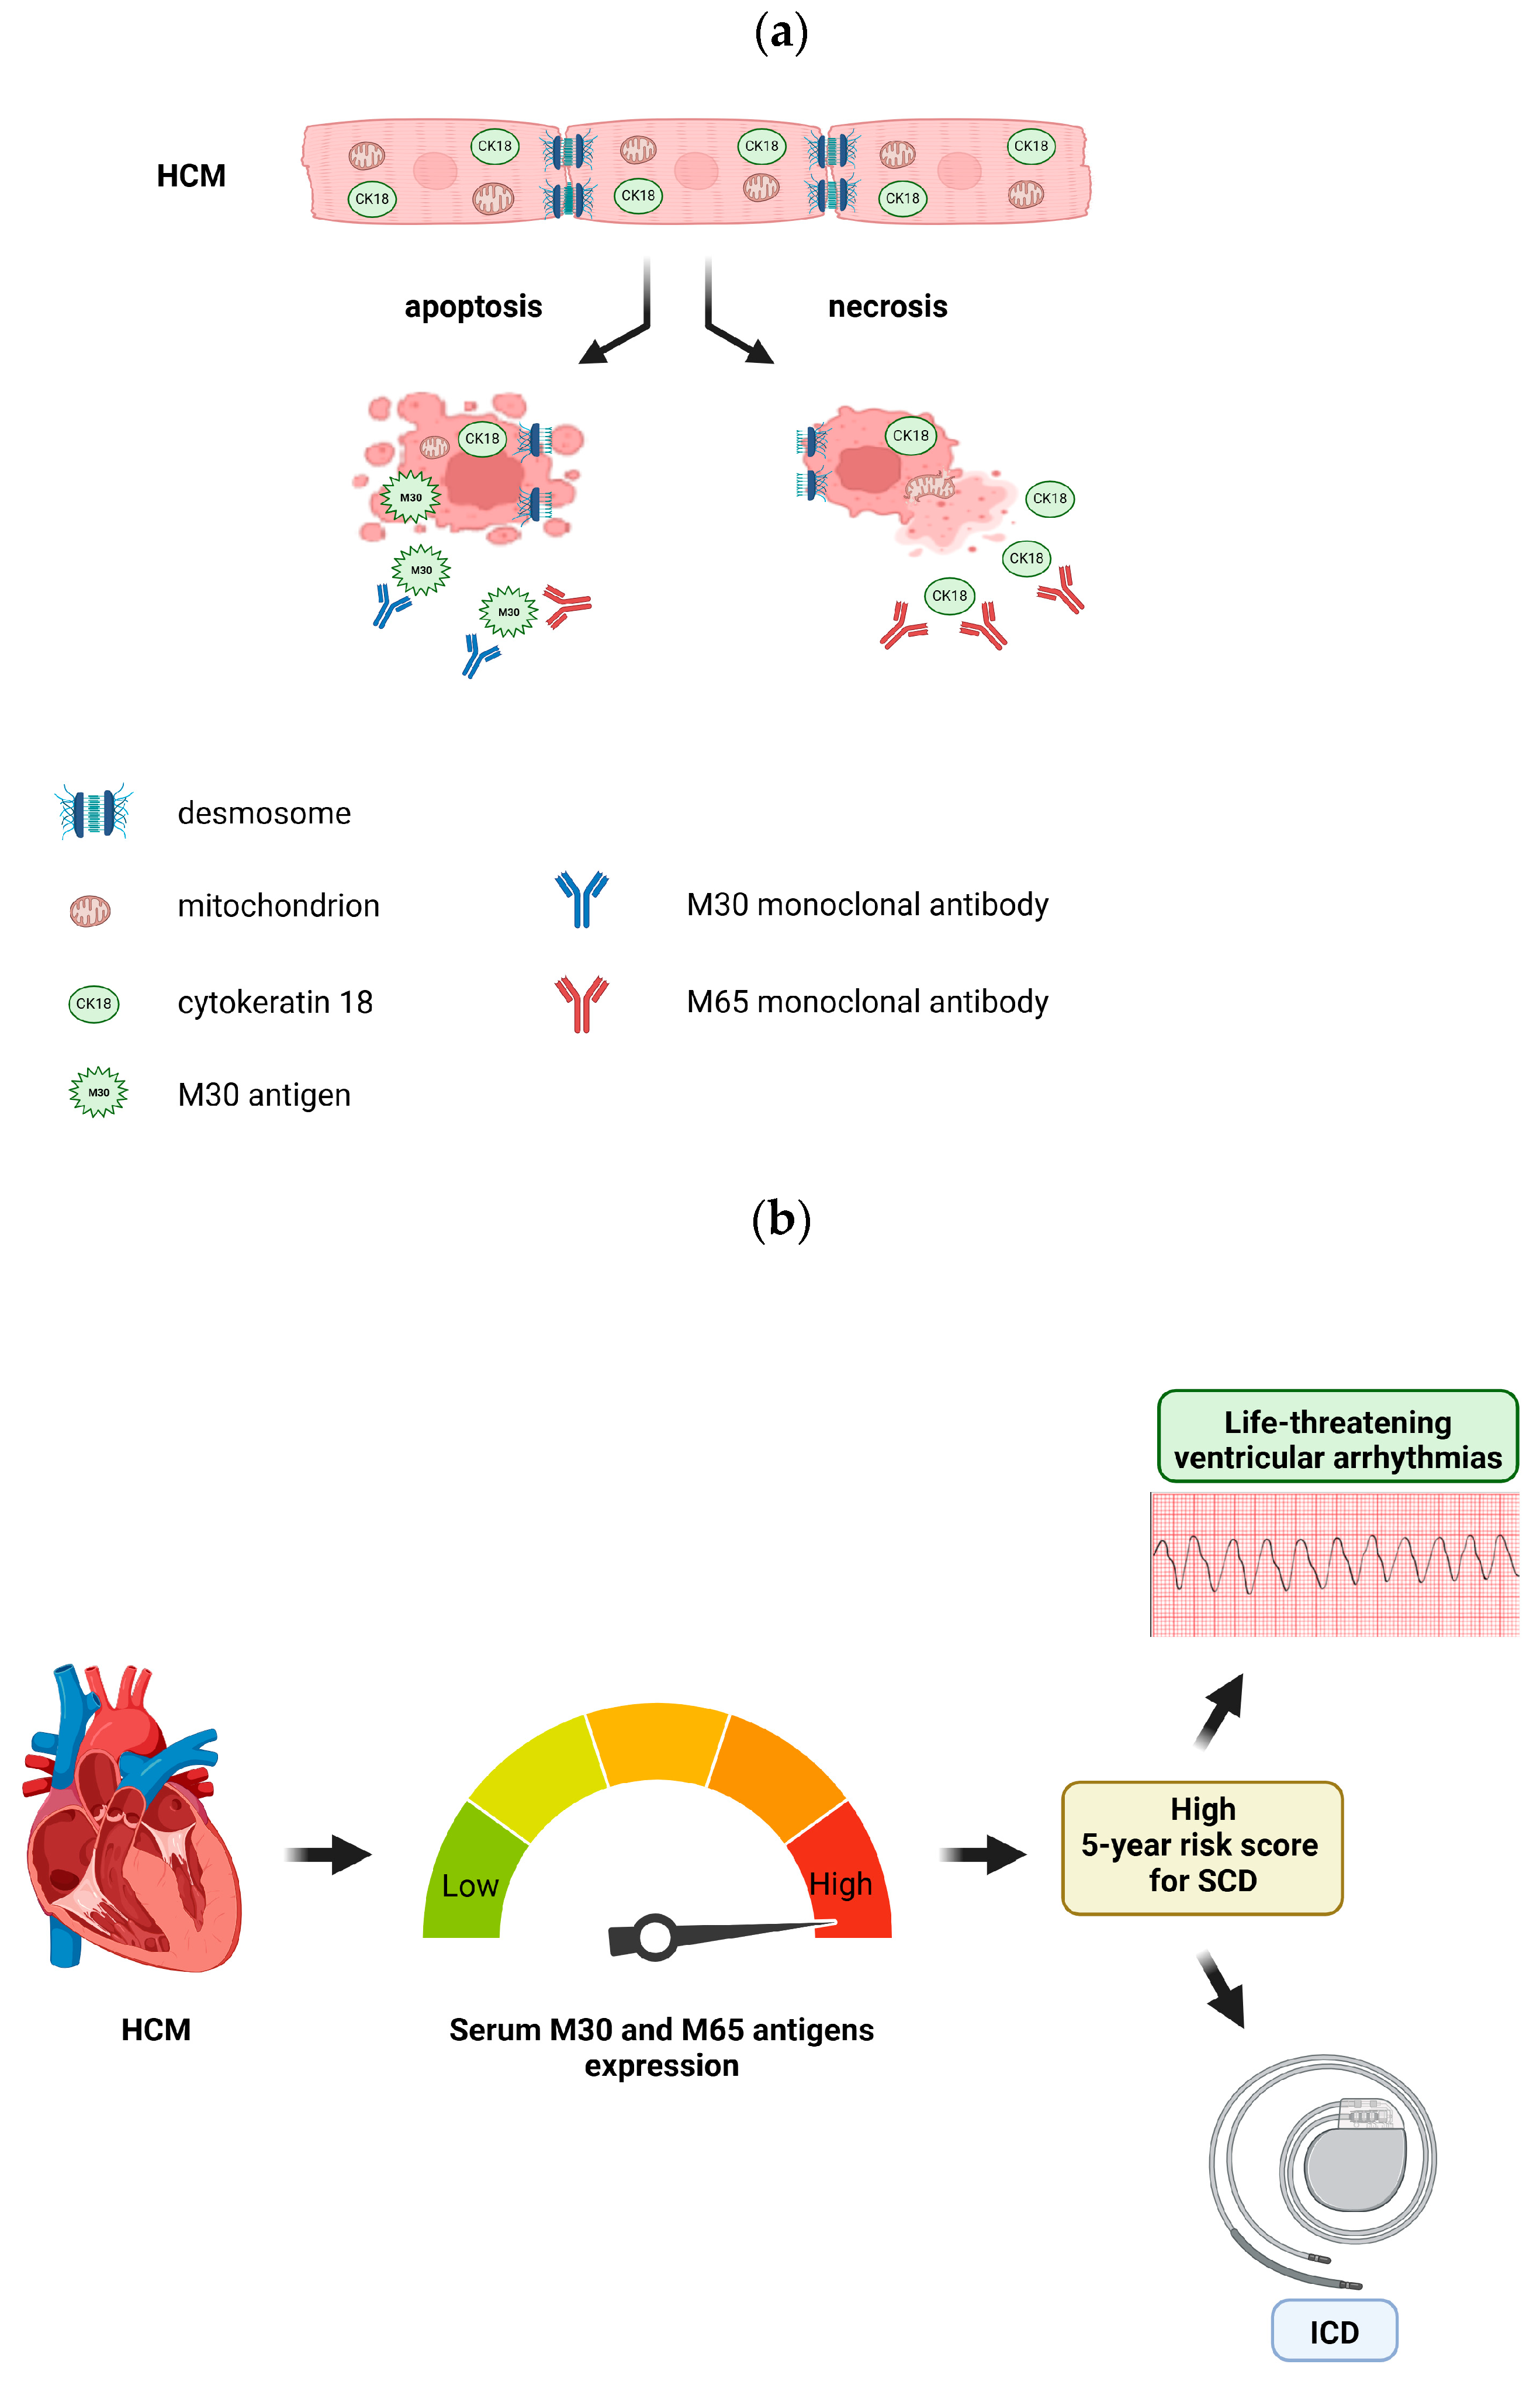

:1. Introduction

3.2. Levels of CK18 and Its Caspase-Cleaved Product in the Blood Serum of Patients with HCM

3.3. M30 and M65 Expression in HCM Group with or without High Risk for SCD

4. Discussion

6. Conclusions